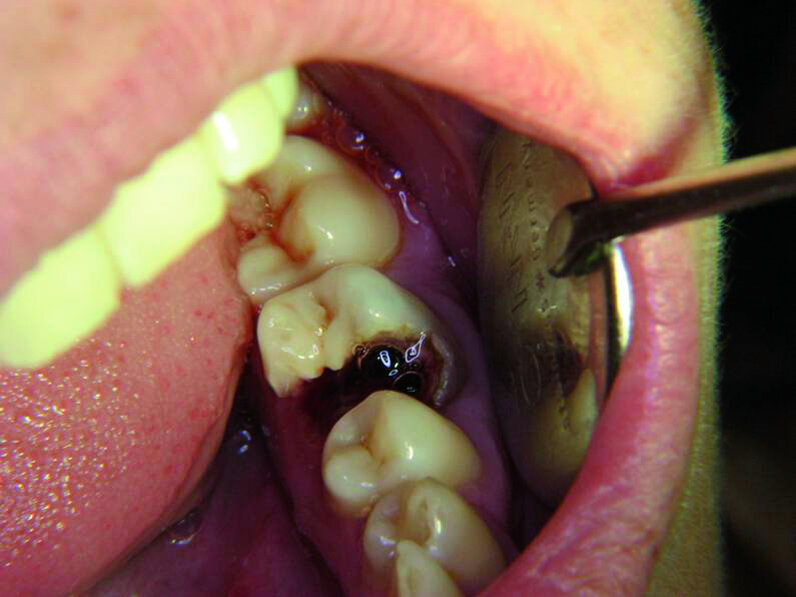

La première molaire supérieure gauche symbolise l’expression de notre sensibilité. Étant donné que cet aspect est souvent réprimé dans notre société moderne, cette dent est aussi très souvent traitée. La première molaire inférieure gauche reflète notre désir d’être aimé. Cette dent est souvent restaurée et est très vite associée à des résultats affligeants. Par exemple, les figures 10a–e montrent une patiente chez qui cette dent s’était fracturée après une rupture sentimentale. Un examen radiographique avait révélé que toutes les autres dents étaient demeurées intactes.